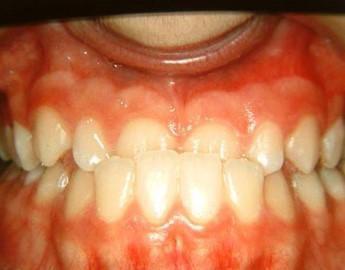

-Προγναθισμόs κάτω γνάθου

Πρώτη περίπτωση

029

Η σημασία της στοματικής υγιεινής και ορθοδοντικής πρόληψης

030

Πριν Μετά

Εάν ο προγναθισμός της κάτω γνάθου δεν αντιμετωπιστεί σε νεαρή ηλικία τότε η διόρθωση του θα χρειαστεί και τη βοήθεια της γναθοπροσωπικής χειρουργικής, διότι όταν η ανάπτυξη τερματιστεί δεν γίνονται γναθικές αλλαγές κατά τη διάρκεια της ορθοδοντικής θεραπείας παρά μόνο μετακινήσεις φατνιακού οστού και δοντιών (19)